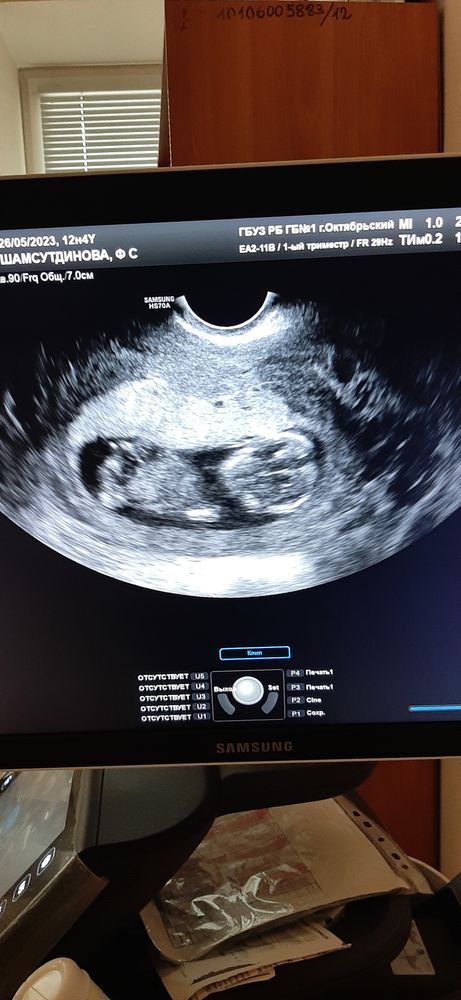

Первый скрининг